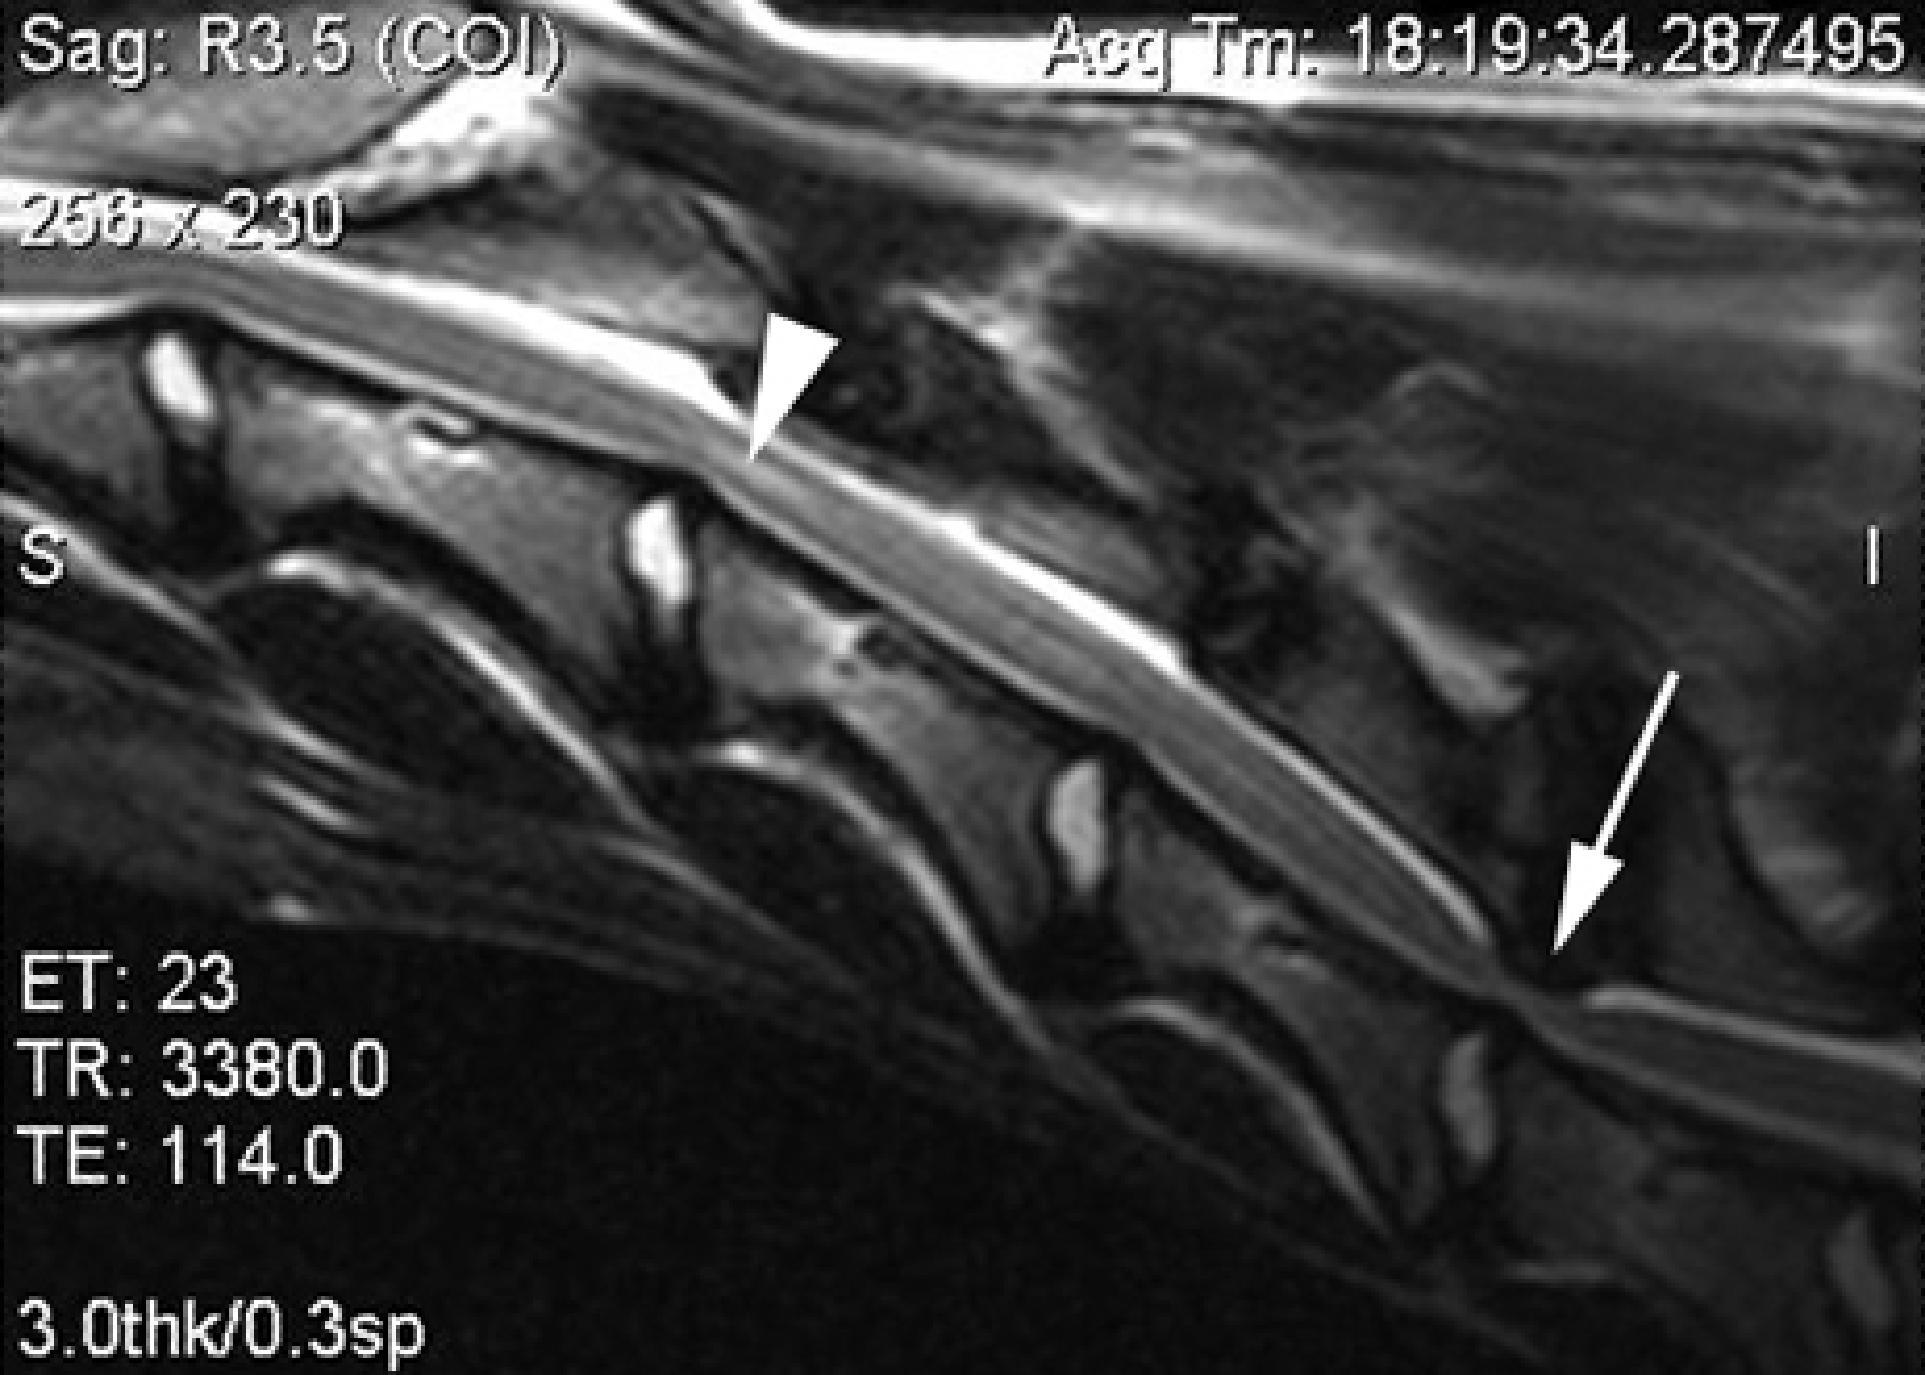

O médico veterinário requerirá os estudos de imagem adequados, como radiografias, ressonância magnética, tomografia computadorizada ou mielografia, para proceder com o diagnóstico diferencial da síndrome de Wobbler, a partir da observação das vértebras cervicais e da coluna. Provavelmente, também levará em consideração o perfil genético de cada cão. Adicionalmente, poderá solicitar análises de sangue e urina completas, para descartar outras possíveis causas patológicas e verificar o sistema imunológico do seu melhor amigo.